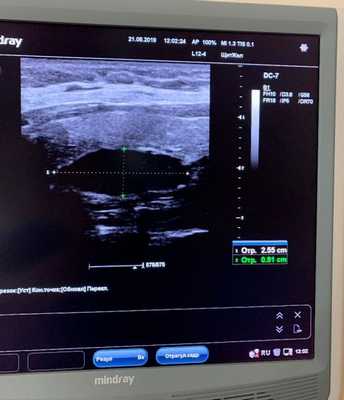

УЗИ щитовидной железы информативно только при расположении паратиреоаденом в типичных местах - в области щитовидной железы.

С целью уточнения природы гиперпаратиреоза и визуализации аденомы выполняется УЗИ щитовидной и паращитовидных желез, термография, сцинтиграфия, артериография, КТ, МРТ. Тонкоигольная биопсия с цитологическим исследованием пунктата позволяет подтвердить диагноз и определить форму аденомы паращитовидной железы.

1. Ультразвуковое исследование

Исследуемая область при УЗИ сверху ограничена бифуркацией (разделением) сонной артерии, снизу — грудинной вырезкой, сбоку — сонной артерией/внутренней ярёмной веной [7] . Паращитовидные железы нормального размера обычно не визуализируются с помощью ультразвука. Аденомы проявляются в виде овальных анэхогенных (выглядят чёрными) или гипоэхогенных (выглядят тёмно-серыми) образований, расположенных кзади от щитовидной железы. Обычно можно увидеть эхогенную (светлую) линию, которая отличает щитовидную железу от увеличенной паращитовидной железы. Более крупные аденомы чаще имеют кистозные изменения.